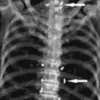

The 65-year-old woman’s X-rays revealed hundreds of tiny specks that doctors learned were gold threads inserted as part of a traditional acupuncture practice

During an X-ray to assess her knee condition, doctors were stunned to discover hundreds of tiny gold threads embedded deep within her joints, a byproduct of a prior acupuncture treatment.

Min-Young Park, a radiologist at Seoul National University Hospital, who reviewed the scans. ‘These threads were so numerous and diffuse that they obscured critical anatomical details, making it harder to assess the full extent of her osteoarthritis.’

The X-ray revealed the threads clustered around her kneecaps, extending into her shin bone and upper thigh—a distribution that could interfere with future diagnostic imaging. ‘This is a textbook example of how alternative treatments can complicate medical care,’ said Dr.